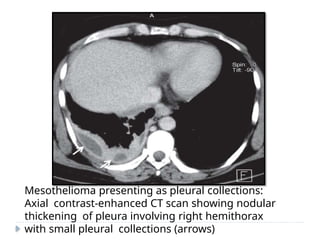

Mesothelioma presenting as pleural collections:

Axial contrast-enhanced CT scan showing nodular

thickening of pleura involving right hemithorax

with small pleural collections (arrows)

Mesothelioma presenting aspleural collections: Axial contrast-enhanced CT scan showing nodular thickening of pleura involving right hemithorax with small pleural collections (arrows)